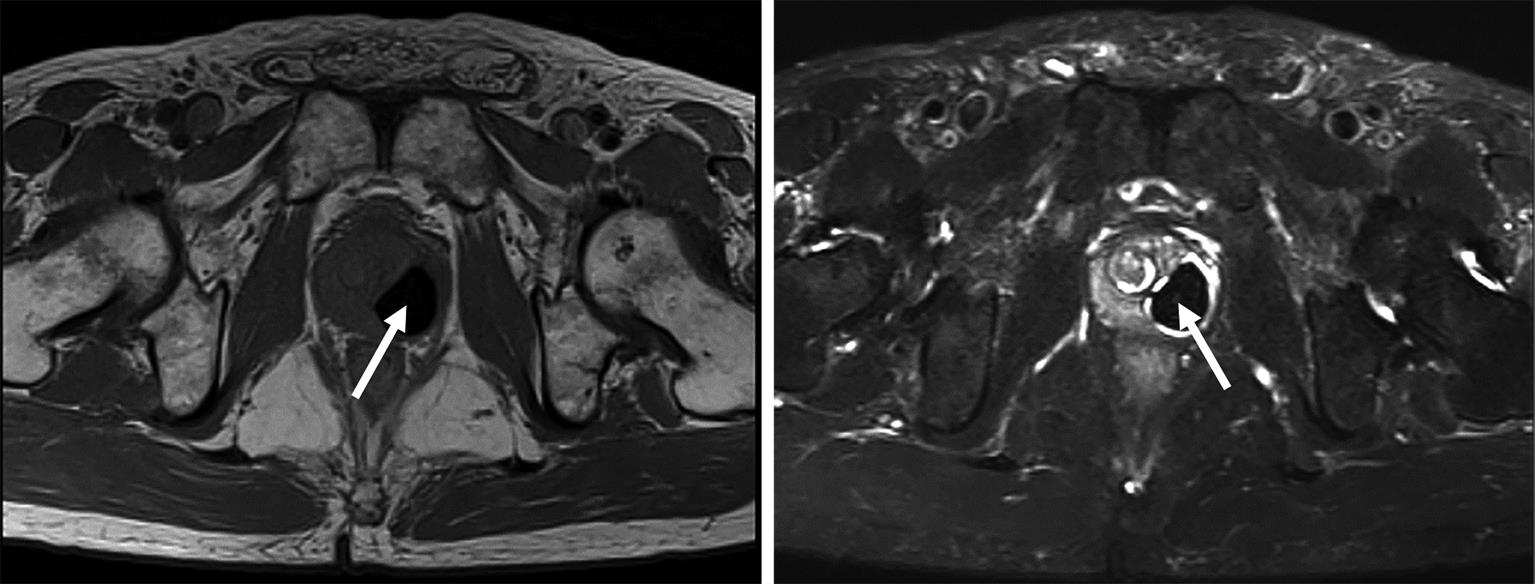

• 3种骶2髂骨螺钉置钉技术准确性的比较研究

2023, 48(11):1381-1386. DOI: 10.13406/j.cnki.cyxb.003371

摘要 (66) HTML (38) PDF 1.13 M (179) 评论 (0) 收藏

摘要:目的 比较传统徒手置钉,3D打印模板引导技术(three-dimensional printed template guided technique,TGT)和ball tip置钉技术在置入骶2髂骨(s2 alar-iliac,S2AI)螺钉的准确性。方法 回顾分析接受S2AI螺钉放置的145例患者,按置钉技术不同将其分为徒手技术组(36例)、TGT技术组(48例)和ball tip技术组(61例)。所有患者术前行骨盆CT确认最佳S2AI螺钉的最佳轨道参数,术后CT扫描评估螺钉轨迹的准确性,比较3种技术的置钉准确性。结果 3组患者S2AI螺钉的最佳轨道参数差异均无统计学意义(P>0.05);3组患者共置入S2AI螺钉290枚。其中,传统徒手技术组72枚,TGT技术组96枚,ball tip技术组122枚。传统徒手组置钉不准确率为18.1%(13/72),TGT技术组置钉不准确率3.1%(3/96),ball tip组置钉不准确率为4.1%(5/122):TGT技术组置钉准确性高于传统徒手技术组,差异有统计学意义(P<0.05);ball tip技术组置钉准确性也高于传统徒手技术组,差异有统计学意义(P<0.05);TGT技术组置钉准确性虽高于ball tip技术组,但差异无统计学意义(P>0.05)。结论 TGT技术和ball tip技术均为S2AI螺钉置入的可靠技术,二者的准确性均明显高于徒手技术,但ball tip技术操作简单。